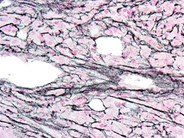

Acute Megakaryoblastic Leukemia flow cytometry​